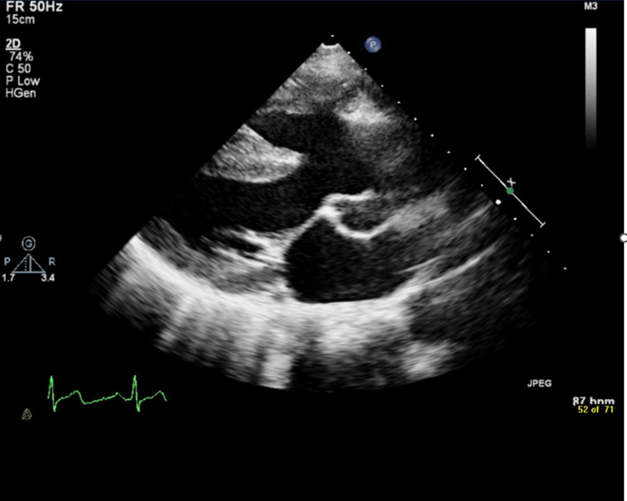

The laboratory test results are summarized in Table 1, and the echocardiographic findings are outlined in Table 2 and illustrated in the accompanying figures (Figure 1)

Figure 1: ECHO showing Large conoventricular VSD with bidirectional shunt Common truncus seen overriding the ventricular septum. (White arrow)